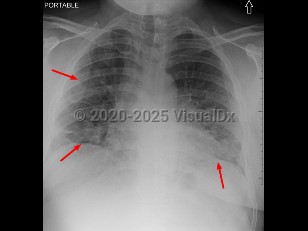

- Severe (dyspnea, hypoxia, or > 50% lung involvement on imaging)

- Critical (respiratory failure, shock, or multiorgan system dysfunction)